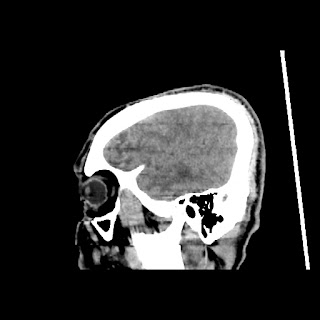

A 60 years old man with seizure since 12 years

Plan CT scan was done on 22 march 2016